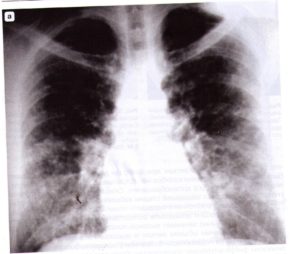

(Слева) На рентгенограмме органов грудной клетки в прямой проекции у мужчины 57 лет с гиперчувствительным пневмонитом 1-й группы («легкие любителя птиц») в обоих легких визуализируются диффузные плохо отграниченные неоднородные участки снижения пневматизации.